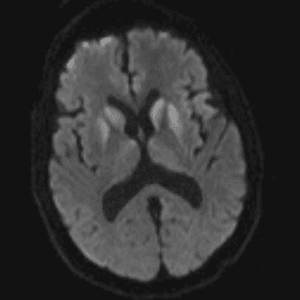

Neurodegenerative Diseases